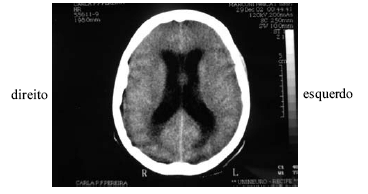

Uma professora de 21 anos de idade apresentou crise convulsiva na fazenda onde dava aulas e, por falta de transporte, somente após quatro horas foi levada ao hospital geral. Ao chegar ao hospital apresentava a seguinte pontuação na escala de coma de glasgow: resposta visual — 3/4, verbal — 3/5 e motora — 4/6. A família revelou que a paciente estava cada vez mais sonolenta e negou sintomas, tais como febre, cefaléia, náuseas, vômitos ou crises epilépticas prévios ao quadro. Foi realizada tomografia de crânio, cujo resultado é mostrado na figura acima, mas não havia neurologista no hospital naquele momento.

No caso hipotético apresentado, a conduta mais prudente consistiria em